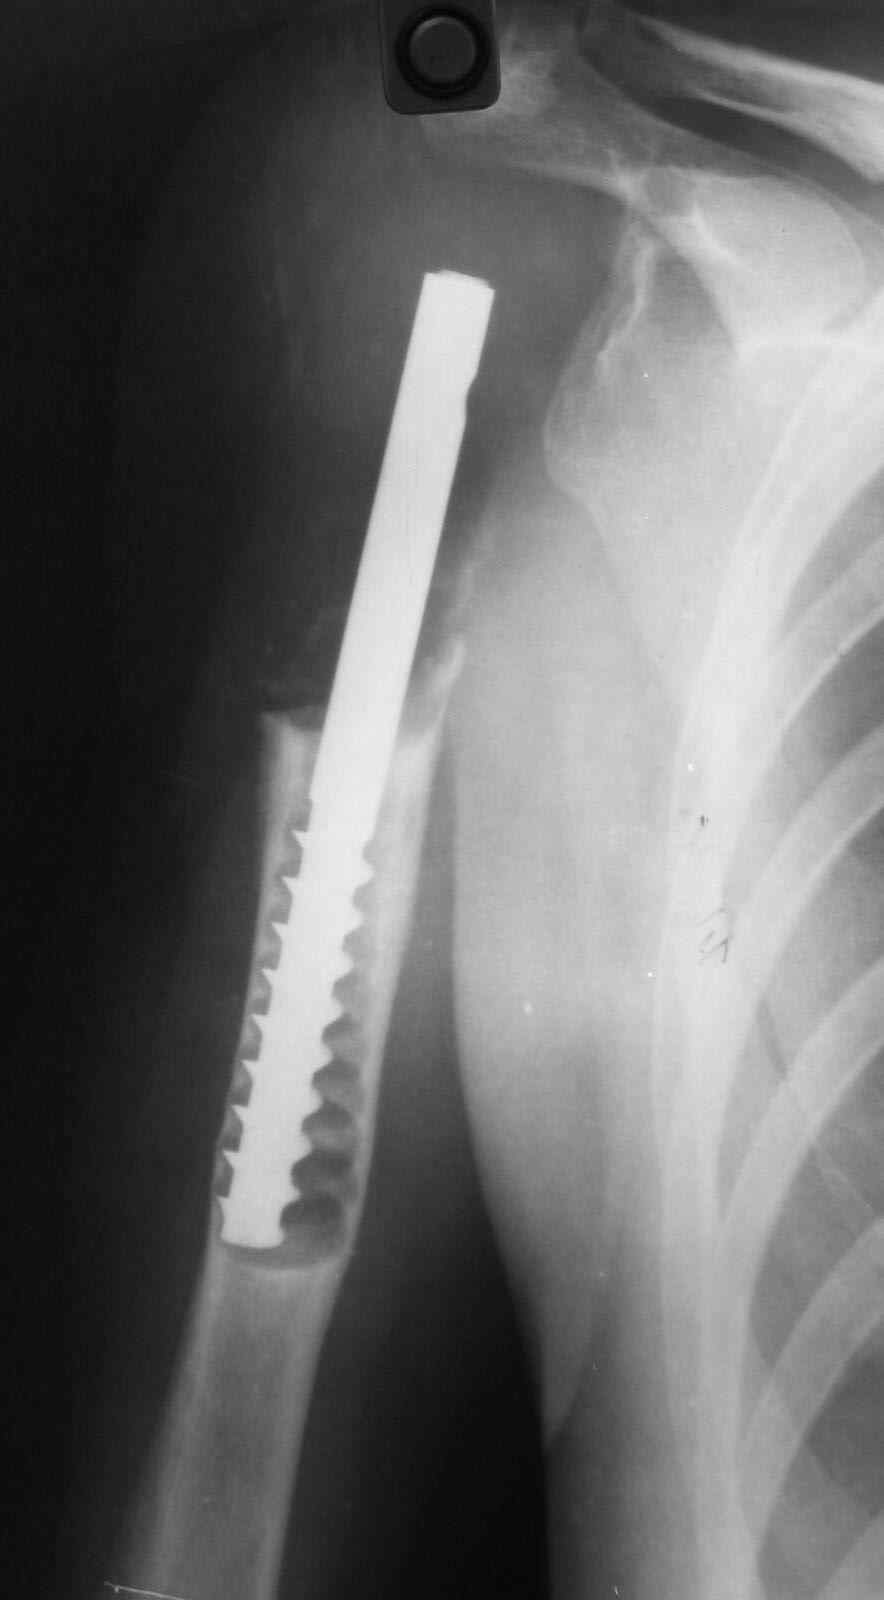

Больная 34 года операрована 14 лет назад по поводу литической формы ОБК головки плечвой кости

14 лет назад больной имлапнтирован протез плечевой кости выполненый по методике Воронцова на штифте-штопоре Сиваша,за 2 года до имлапнатации в онкологическом учереждении больной выполнена резекция проксимальоной части плечевой кости по поводу ОБК, ксенотрансплантации головки, и последующем его удалением на фоне гнойного процесса. У больной имелся втянутый обширный рубец и болтающееся плечо, афункциональная верхняя конечность, выраженный косметический дефект.П/опрационный период без осложнений, сохранялась выраженная контрактура в плечевом суставе, но стаилизация плеча и косметический эффект больную устраивал,даллее контакт с больной был утерян ( поменяла место жителсьтва. Через 14 лет полноценной жизни сельской жешщины ,больная нашла нас с клиникой выраженной нестабильности протеза. Категорически отказалась от замены протеза.

Выполнена операция- малоинвазивно проведена LCP пластина в образованный канал над головкой протеза, фиксирована к протезу и дистально к плечевой кости, на зоной резорбции трепонирована кость, удалена соединительно-тканная оболочка, полость заполнена chronOS. П/о период без осложнений, клиника нестабильность купирована.Прошло 2 года по телефону сообщила, что у нее все хорошо, продолжает жить счастливой жизнью сельской труженицы

Головка отлита из акрилоксида( то чем мы располагали в прошлом веке), он полность Р-прозрачен, по методике Воронцова рекомендовалось добавлять Р-контрастные добавки,например сульфат бария, учитывая, что он давал раковины в полимере, мы это не сделали.Кстати, довольно крепкий получился, затупили 2 сверла.

Функциональный результат нам известен в полеоперационном периоде

отведение 10 гр, сгибание 60 гр, разгибание 0, ротация 5гр, что соответсвовало функции до наступления нестабильности.

К сожаления, вся информация о нынешем состоянии больной получена по телефону - болей нет, объм движения не уменьшился, полная нагрузка на конечность, из наших рекомендаций по ограничениям соблюдает только одно- не выкручивает белье.